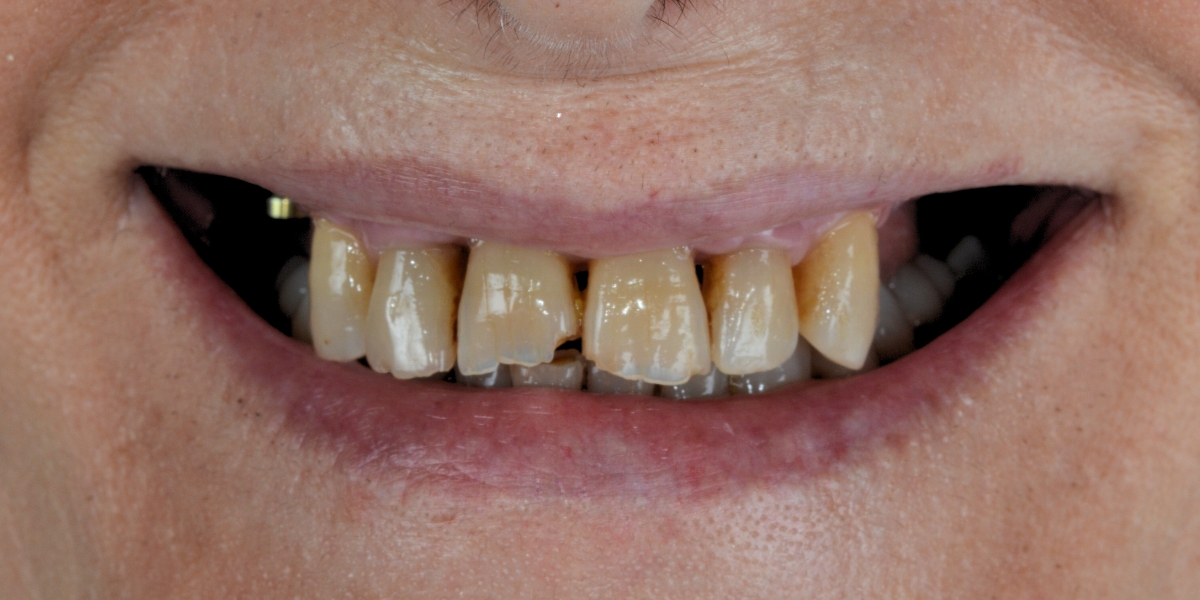

Smiles we’ve transformed through implant treatments

Every smile tells a story, and at RM Odontología, we have many to share. Here are a few real-life cases from our clinic.